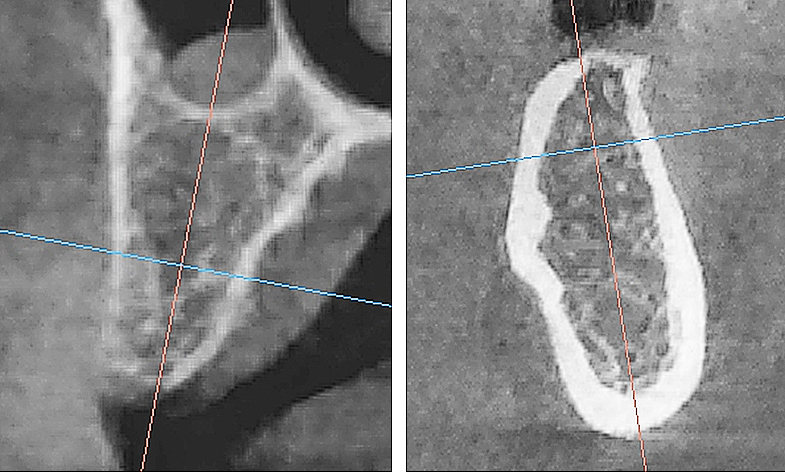

Рис. 1. Поперечный срез микротомографии локтевого отростка овцы

Учитывая выше перечисленные недостатки, поиск новых областей и способов хирургического доступа для создания экспериментальной модели исследования остеопластических материалов является актуальным. Нас заинтересовало использование в качестве экспериментальной живой модели область локтевого отростка передних конечностей овцы. В доступной литературе нами не встречено упоминаний об использовании локтевых отростков овец с целью формирования костных дефектов для оценки регенераторного потенциала остеопластических материалов. Вероятно, это обусловлено боязнью риска травматизма локтевого отростка в ходе формировании дефекта при использовании классического хирургического инструментария – сверл и фрез большого диаметра. Между тем очевиден ряд преимуществ данной области – схожее анатомическое строение и архитектоника с альвеолярной частью челюстей человека. Локтевой отросток имеет наружный кортикальный слой и внутренний, представленный губчатым веществом с костномозговыми пространствами небольшого размера (рис. 1, 2).

Рис. 2. Поперечный срез альвеолярной кости верхней челюсти человека в проекции отсутствующего премоляра (А) и альвеолярная кость нижней челюсти человека в проекции отсутствующего моляра (Б). 3D-КЛКТ